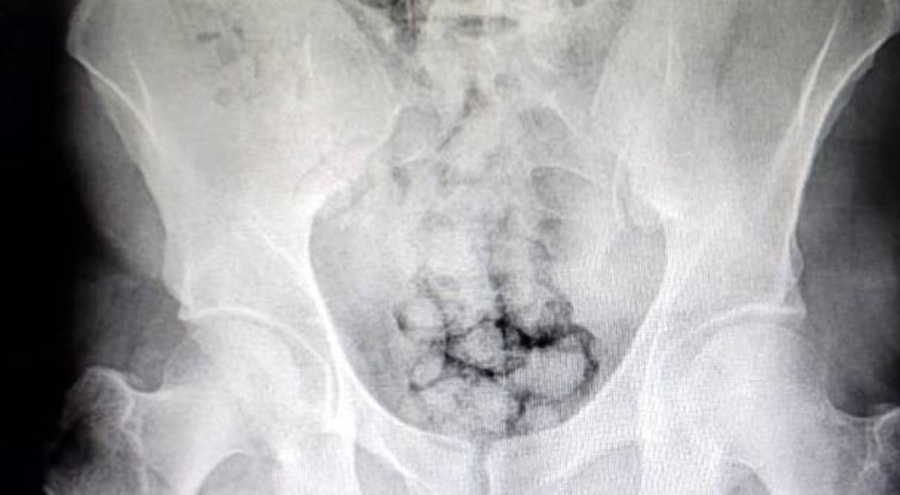

Kayseri'de polis ekiplerince düzenlenen uyuşturucu operasyonunda, midesinde yaklaşık 60 kapsül uyuşturucu taşıyan 2 şüpheli yakalandı. Uyuşturucular röntgen çekimi ile görüldü.

Şüphelilerin bulunduğu araç durduruldu. Muayene edilmek üzere Kayseri Devlet Hastanesi'ne getirilen 2 şüphelinin röntgenleri çekildi. Röntgen çekimi sonrası şüphelilerin midesinde yaklaşık 60 kapsül içinde toplam 500 gram metamfetamin olduğu tespit edildi.